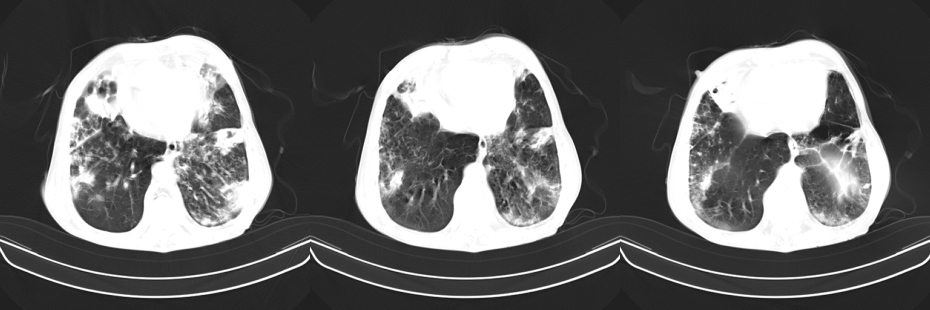

以下是引用mzh123在2007-8-26 19:58:00的发言:[br]两肺弥漫性斑片改变,其中可见大小不等之不规则空洞,结合既往病史还是考虑结核复发及感染。

以下是引用云翔在2007-8-26 20:54:00的发言:[br]这是44岁的肺吗?是否有先天病的基础?干酪性肺炎?